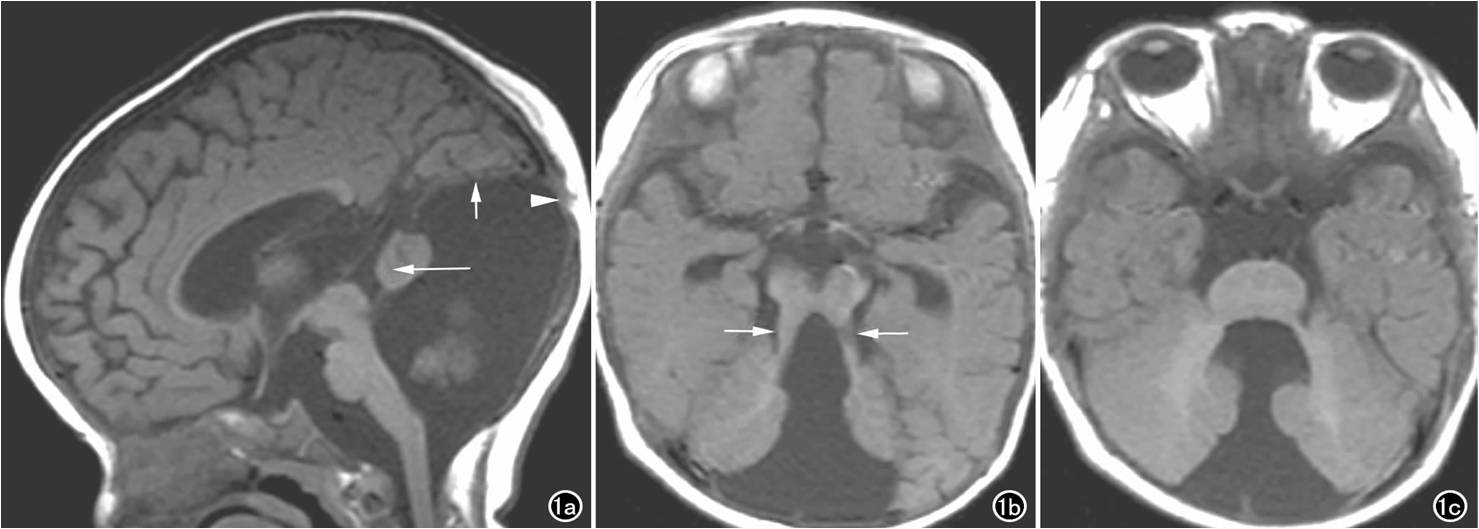

(六) Dandy-Walker畸形:為小腦蚓部發(fā)育不良,原始第四腦室頂部的上部膜性區(qū)永存,第四腦室囊性擴張所致。

男,6個月,Dandy-Walker畸形。T1WI矢狀面圖像示后顱窩擴大,第四腦室囊性擴張,小腦蚓部小,殘存小腦蚓似團塊狀向上旋轉(zhuǎn)、移位(長箭),小腦幕、直竇及竇匯抬高(短箭)。同時可見枕部皮下囊性竇道與顱內(nèi)相溝通(箭頭)。